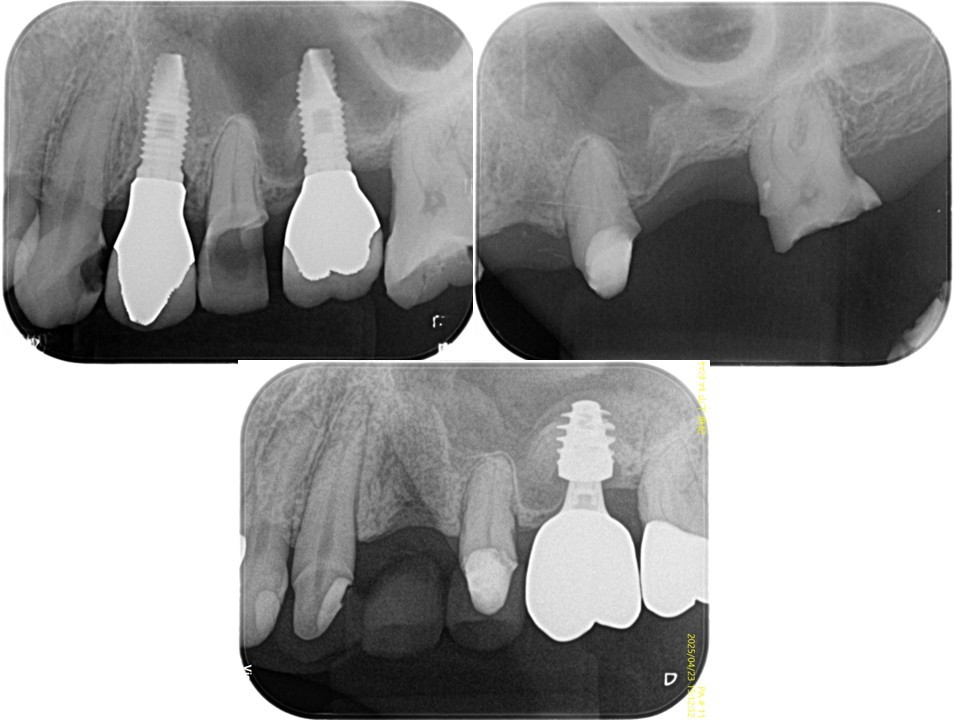

(図19)初診時のレントゲン所見

ほとんどが有髄歯であり無髄歯は左上1番と左下6番のみ左下6番は歯根破折しており抜歯を予定

(図20)

う蝕が大きく進行した右上5番、左上3・5番、右下5番、左下5番、右上5番、左上3・5番、左下5番の隣在歯としてインプラント治療を予定しており、感覚受容器が乏しいエリアになることが理由でVPTにより有髄歯で保存することを目指した

(図21)右上5番の治療経過

近遠心にインプラントが存在し、右上5番が有髄歯で存在することで感覚受容器を正常な状態で保てている

(図22)左上3・5番の治療経過

左上5番も近遠心にインプラントが存在し、左上5番が有髄歯で存在することで感覚受容器を正常な状態で保てている

(図23)左下5番の治療経過

遠心にインプラントが存在し、左下5番が有髄歯で存在することで感覚受容器を正常な状態で保てている

(図24)右下5番の治療経過

(図25)治療経過

上4番のインプラント再埋入待ちの補綴装置装着状態

(図26)術後レントゲン像

左上1番以外は天然歯は全て有髄歯の状態で保存できている